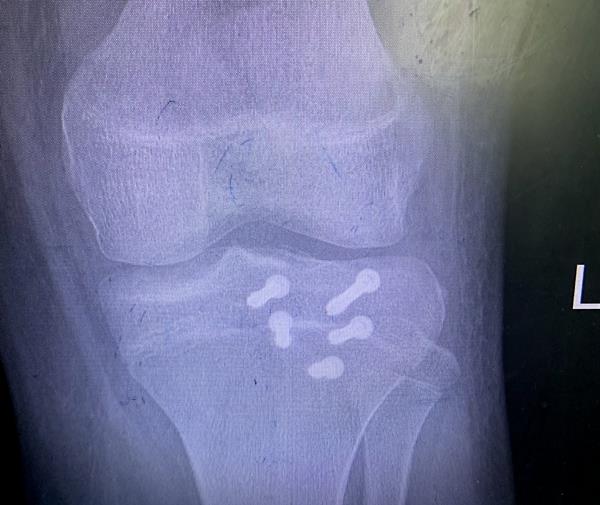

患者脛骨結(jié)節(jié)撕脫骨折影像

這次收治的患者屬于Ogden 3A型,手術(shù)指征明確,手術(shù)團隊采用骨折端切開復位空心釘內(nèi)固定+髕韌帶可吸收錨釘重建術(shù)+經(jīng)膝關(guān)節(jié)鏡探查、清理的手術(shù)方式,獲得滿意效果。